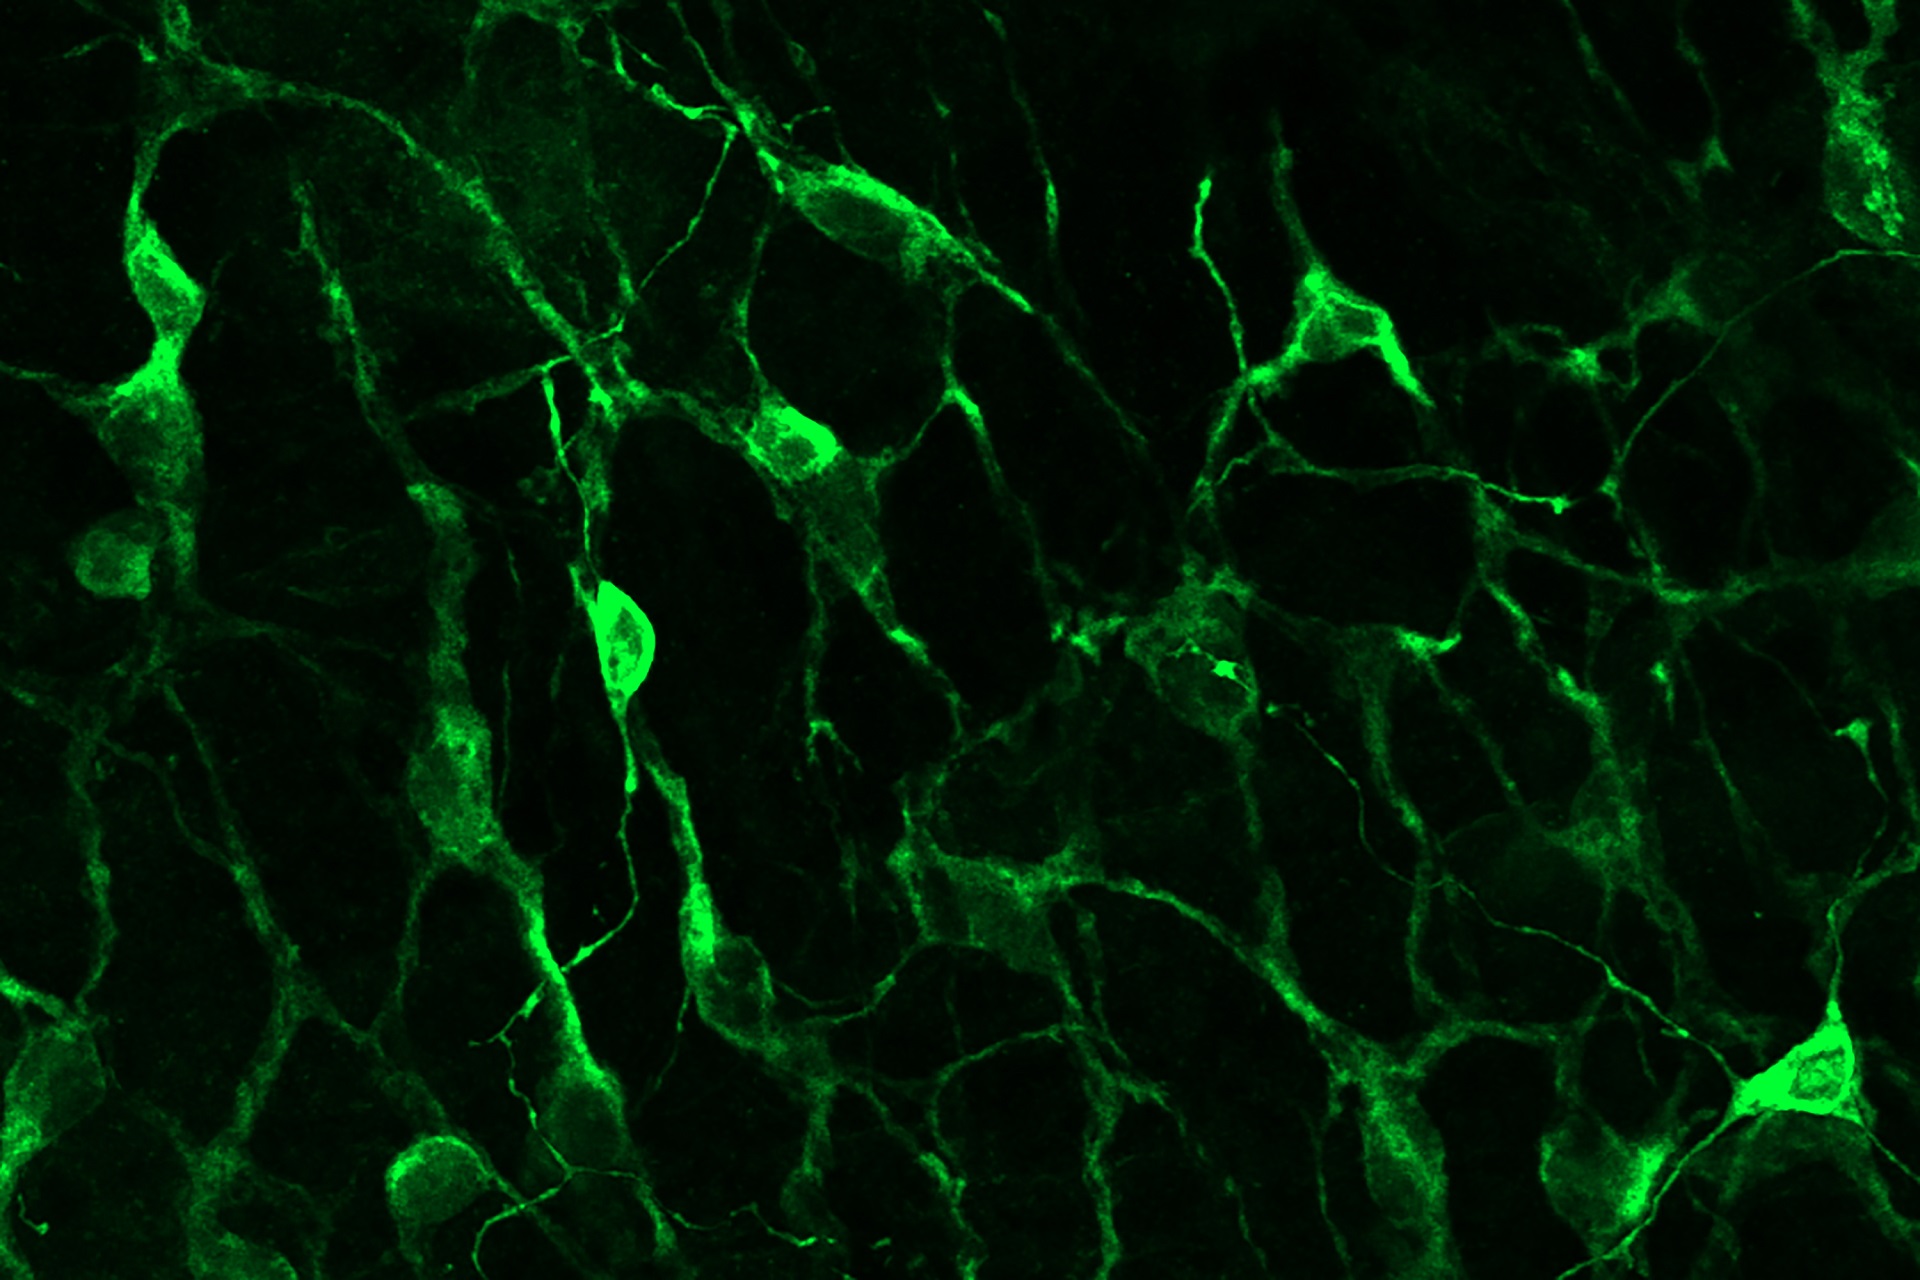

Forschende haben bei Fruchtfliegen neuronale Schaltkreise und Mechanismen entdeckt, die dafür sorgen, dass auch bei schnell veränderten Lichtverhältnissen gut gesehen wird.